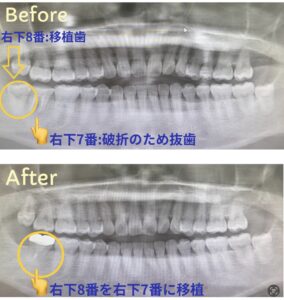

今回は親知らずの移植の症例のご紹介です😊

こちらの症例は右下7番が根管破折の為保存不可の状態でしたので、

右下7番を抜歯し、

右下8番(親知らず)を移植しました。